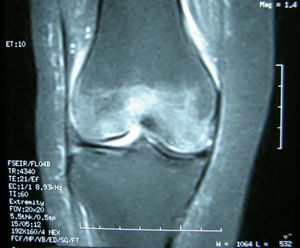

Pruebas complementarias. El estudio radiológico inicial mostró una radiolucencia difusa de la metáfisis y la epífisis femoral distal, sin líneas de fractura; el espacio articular permanecía normal (fig. 1). La resonancia magnética (RM) mostraba un extenso edema óseo en la epífisis femoral distal, más marcado en cóndilo externo, con disminución de la señal en T1 y aumento en T2, además de un pequeño derrame articular difuso (fig. 2).

Horas después de realizarse estas pruebas, la paciente sufrió una caída fortuita, refiriendo de forma inmediata dolor intenso e impotencia funcional en la rodilla derecha. El estudio radiológico urgente mostró una fractura patológica supracondílea del fémur derecho (fig. 3).